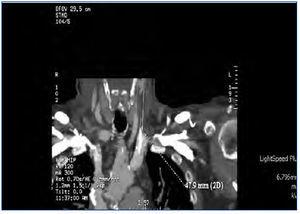

Se decide suspender la heparina ante la sospecha de TIH II, transcurriendo las sesiones sucesivas con múltiples problemas de flujos y resistencias del catéter, aparte de coagulaciones repetidas del circuito. A la espera de tratamiento con argatroban, se recambia el catéter yugular tunelizado por otro de similares características, sin mejorar el rendimiento, por lo que se realiza tomografía axial computarizada cervical, informando como trombosis parcial de la vena yugular izquierda (figura 2 y figura 3). Dos días más tarde el paciente acude asintomático a la unidad, pero a los 10 minutos de su conexión experimenta un nuevo episodio de disnea súbita con p02 de 78 %, de la que se recupera con medidas de soporte habituales en el transcurso de 1 hora, no precisando ingreso hospitalario. El recuento de plaquetas es de 101 x 109/l, inferior al de los días previos. Cuarenta y ocho horas más tarde las plaquetas son 162 x 109/l. Finalmente se consigue disponer de argatroban, que se administra a la dosis descrita previamente de 2590 mic/kg en bolo al iniciar la sesión y en perfusión posterior de 2 mic/kg/min, finalizando 1 hora antes de la desconexión. Los controles de : tiempo de tromboplastina parcial activada (TTPA) se mantuvieron en los márgenes recomendados de 1,5 a 2,5 sobre el basal. A partir de ahí desaparecieron las coagulaciones del circuito y el rendimiento del mismo catéter fue excelente. Durante la espera al inicio del tratamiento con el inhibidor de trombina, así como después hasta que el paciente finalmente inició diálisis peritoneal, se prescribió tratamiento antiagregante con clopidogrel. Se explica por la amenaza de nuevas punciones de vasos centrales y dos intervenciones quirúrgicas pendientes: catéter peritoneal y resección transuretral de pequeño tumor vesical, si bien esta última se realizó ya iniciada la diálisis peritoneal. En ningún momento antes de su transferencia al centro de referencia para el cambio de la terapia sustitutiva se administraron conjuntamente argatroban y dicumarínicos. Hay que señalar la ausencia de datos de trombosis venosa aguda y que la frecuencia cardíaca estaba controlada.

Figura 3. Trombosis de vena yugular (vista frontal).